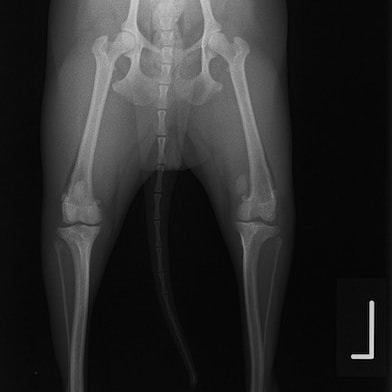

■ 症例22 ポメラニアン 1歳5か月 去勢雄

左後肢の挙上を主訴に来院した。整形学的検査、レントゲン検査より左右の膝蓋骨脱臼(左GradeⅡ〜Ⅲ、右Grade Ⅱ)を認めた。また、脛骨の前方引き出し試験の際に、引き出し兆候は認められないものの、疼痛が認められたため、前十字靭帯の損傷が疑われた。術中における、目視および関節内の操作によって、前十字靭帯の損傷や過伸展といった異常が認められなかったため、膝蓋骨脱臼の整復のみ実施した。手術手技は縫工筋及び内側広筋の解放、脛骨粗面の外側転位、滑車ブロック形造溝術、内外側関節包の縫縮を実施した。本症例は跛行もなく経過良好である。しかし、頸骨高平部の角度(TPA)が 右26.2°、左24.9°であり、解剖学的に前十字靭帯損傷のリスクが高いことから今後の経過に注意が必要である。